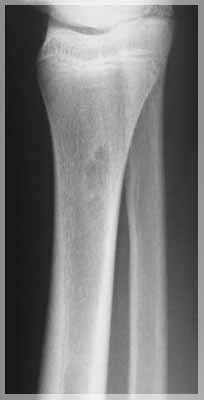

Во второй группе было 11 детей с диагнозами: костная киста трубчатой кости, патологический перелом кости, остеомиелит с разрушением головки бедренной кости. Возраст больных детей составлял от 11 месяцев до 16 лет. Рентгенологически отчетливо прослеживались патологические изменения и дефекты костных тканей. Общепринятые методики требовали хирургического вмешательства. В трех случаях требовалось протезирование с заменой костной ткани, что влекло за собой инвалидность и нарушение общего развития опорно-двигательного аппарата ребенка. В двух других случаях ранее было проведено оперативное лечение кисты. После операции наблюдался рецидив и дальнейшее прогрессирование заболевания.

Во второй группе в апреле 2004 г. длительность лечения составила от 6 до 10 месяцев. Во всех случаях наблюдалась положительная динамика. Для 9 пациентов из 11 по характеру восстановления костных тканей можно прогнозировать дальнейшее улучшение до полного излечения. Двое детей, у которых наблюдался рецидив после оперативного лечения, в настоящее время полностью здоровы.